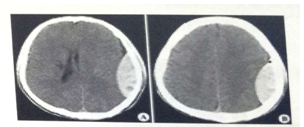

試題2:男,44歲。頭部外傷12小時。結(jié)合CT片,此診斷為(2分)

A.硬膜下血腫

B.腦出血

C.硬膜外血腫

D.顱骨骨折

E.腦血栓

答案:C